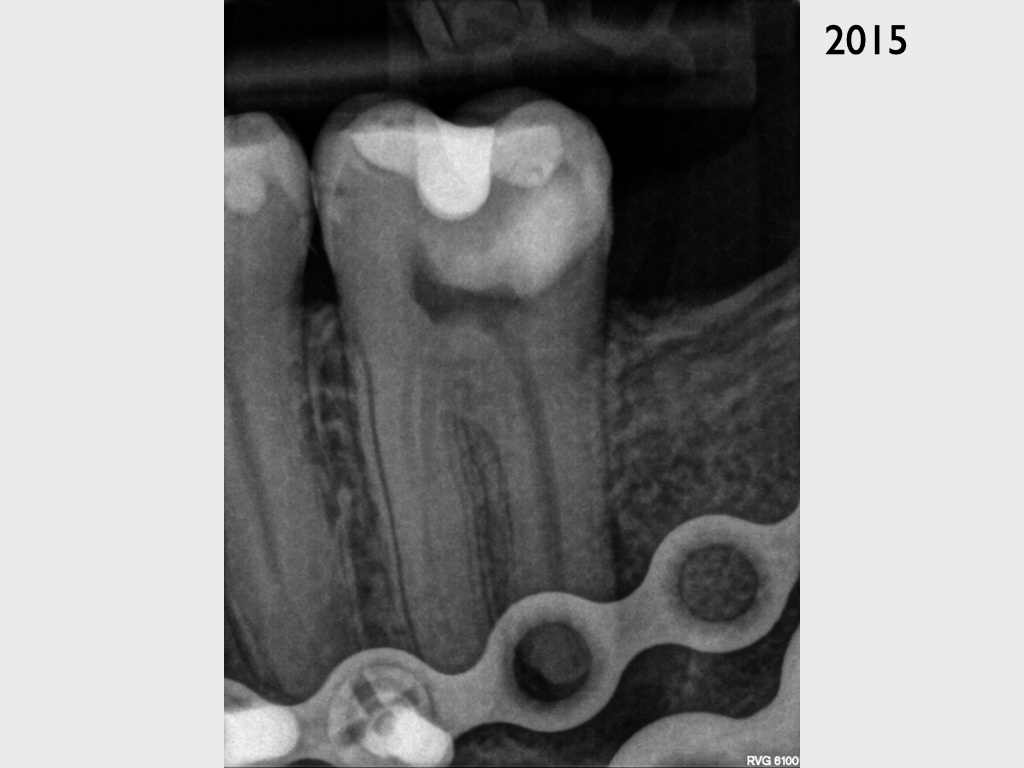

Zielschiessen